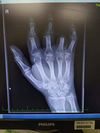

• rumik

Ukazováček bolel jak čert i měl tendenci se prohýbat tak jsem zašel raději do nemocnice a hle? Srostlý vůbec není. Koneckonců mrkněte na rtg.

Čili koncem února jdu k nějakýmu borcovi co tam zkusí dát nějaký vnitřní šroub. Ale kost je už hodně řídká a bůh ví jak to bude držet. Už mne jebne z té ruky.

V březnu podám hlášení.

Doufejme, že to držet bude. Nejsem odborník, ale možná i oni by řekli, že výsledek jistý není. Na rtg je patrné, že kost nesrostla, tedy že nesrostly ty dvě kosti těch článku k sobě, Pokud to spojí nějakým kovem zevnitř, snad to držet bude a časem i sroste. Stav zcela ideální není, ale krom jednoho prstu ty ostatní přišily a ač to vypadalo dosti zle, tak pryč šel jen ten jeden. Pohyblivost je omezená, ale ty prsty tam jsou. U těch přišitých prstů není snad nikdy výsledek stoprocentní jako předtím, bývají tam různá omezení.